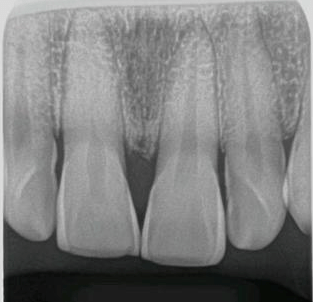

健康的牙片,正常健康的牙片图片

正常健康的牙片图片

健康的牙片图

牙片图片